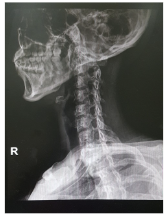

목디스크 증상 원인 치료방법 등 목 디스크 관련 정보에 대해 알아보도록 하겠습니다. 목디스크는 인간의 척추 중 경추부나 흉추부에 위치한 디스크(틀니)가 변형되어 생긴 질환으로, 경추부의 경우 목의 통증, 저림 혹은 근육 경련, 어깨와 팔의 통증, 감각상실 등이 나타나며, 흉추부의 경우 흉부의 통증, 등의 통증 등이 나타납니다. 보통은 원인불명성으로 인한 자연적인 회복을 기다리는 것이 가장 좋으며, 통증이 심한 경우 보조적으로 항통제나 근육 이완제 등을 사용합니다. 만약 압력이 심한 경우 수술이 필요할 수 있습니다.예방법으로는 바른 자세 유지와 체중 조절, 충분한 운동, 목과 등의 근육 강화 등이 있습니다.

목 디스크의 치료 방법은 디스크의 위치, 변형 정도, 환자의 건강 상태 등에 따라 다양합니다. 보통 디스크 변형이 미미하면 안정적인 자세와 통증 조절제, 근육 이완제, 물리치료 등으로 치료할 수 있습니다. 하지만 디스크 변형이 심한 경우 수술이 필요할 수 있습니다. 아래는 일반적으로 사용되는 목 디스크의 치료 방법입니다.